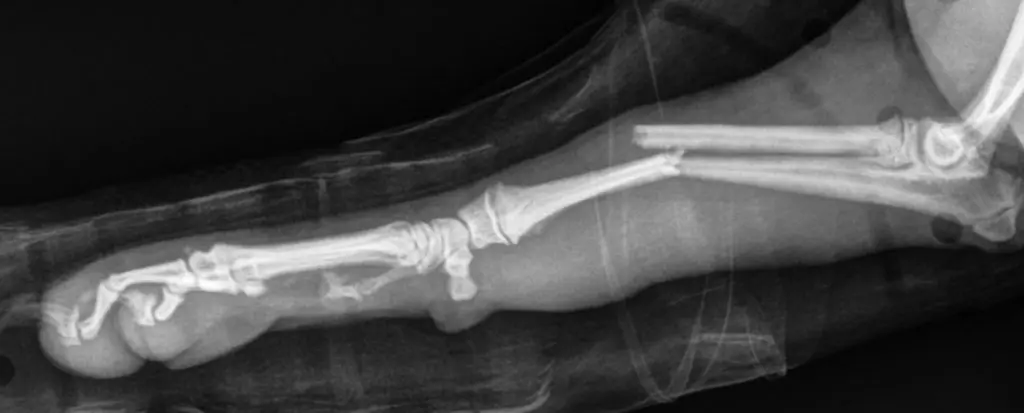

Brain Teaser: Can you solve this puzzle?January 7, 2026Presentation: A five-month-old intact female Pomeranian with right forelimb lameness after jumping off a step.